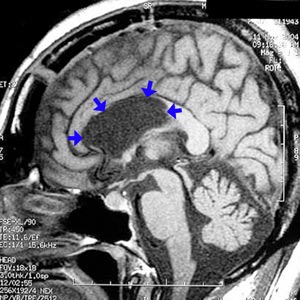

Figura 100 - Ressonância nuclear magnética do encéfalo (normal) antes da cirurgia.

Figura 102 - Ressonância nuclear magnética do encéfalo depois da cirurgia demonstrando a interrupção de 2/3 anteriores do corpo caloso (setas azuis)